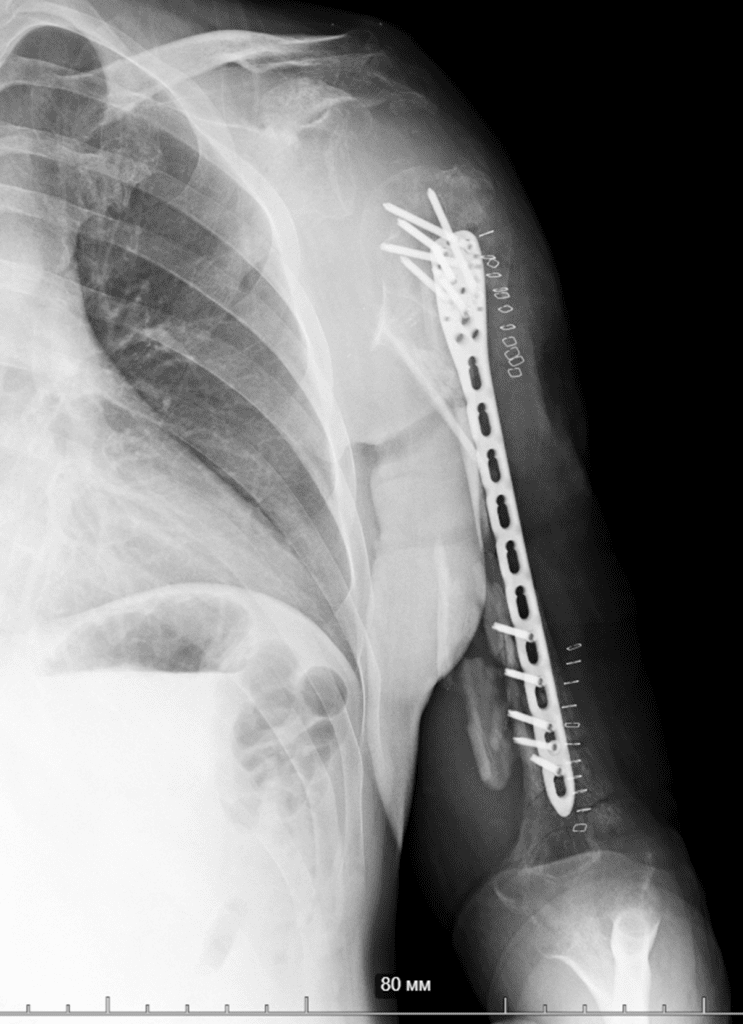

So, together with Vasyl Parii and Denys Dolgush, instead of performing massive bone grafting immediately, we decided to stabilize the severely damaged humerus (see X-rays) with a plate using a minimally invasive approach — and took new tissue samples for culture. In peacetime and in case of a normal civilian injury (usually the main bacteria in such cases is Staphylococcus Aureus), we would do bone grafting simultaneously with internal fixation. But the presence of the “Iraqi bacteria” in early investigations does not allow this; the risk of severe complications is too high.

If the cultures come back sterile, we’ll proceed with the grafting.

If not, we’ll continue with aggressive antibiotic therapy.

Then, surgery on the brachial plexus will be necessary (there is a nerve injury).

If all goes well, we will work with the patient to determine what to do about the shoulder joint.

Most likely, it will need to be fused (arthrodesis surgical procedure) — the deltoid muscle and parts of the rotator cuff are missing, and we still don’t know the full extent of nerve recovery (although there’s some positive progress).

We’ll see.